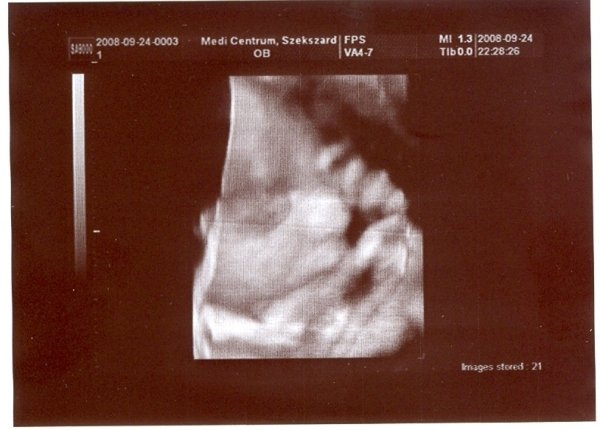

30. hét: Kép Kép

Bernuska: nekem csak a doki magánrendelésén van UH. Én nem járok máshová. Kérdeztem erről a védőnőt is, de ő azt mondta a doki elég. Mondjuk ott nagyon jó minőségű UH van, a környék legjobb 4D-se (amúgy is csak a kórházban van, az meg pocsék). Szívhangot nem néz, de a védőnő mindig nézi. Most azért is mért a doki, mert ez protokoll UH volt, így a 30 .hét környékén, a súlyt csak saccolta, de azt mondta, hogy ott nagyot lehet bukni. 3 hete például megnézte a méhszájamat, és akkor is UH-zott csak nem mért. Akkor végignézte a feje búbjától a kis talpáig az egész gyerkőcöt, és ott külön megnézte a szívét. Ja és mindjárt az elején mikor megnézte a fejecskéjét áttette 4D-re és akkor kaptunk róla egy szép képet. Most is megvizsgált, tökéletesen zárt minden, aztán UH-zott. Megint a fejével kezdte, átrakta 4D-re, úgy nézegettük egy kicsit és jókat nevettünk a dokival. Teljesen eltakarta magát a gyerek és fintorgott. A doki is megjegyezte, hogy milyen kis helyes. Aztán nagy nehezen az egyik kezét elhúzta, és azt a képet kinyomtatta a doki (nemsokára felteszem), Ezután visszakapcsolta sima UH-ra és megmérte! Utána meg kérdezhettem, amit akarok. Nagyon-nagyon segítőkész a dokim, bármikor hívhatom. Pedig én nagyon féltem, mert nincs még egy éve hogy hozzá járok. Előtte 10 évig egy másik dokihoz jártam, akit nagyon szerettem, de elment nyugdíjba és szülést nem vállal. Akkor találtam rá a mostanira. Eddig minden ok vele. Ja és szerintem nem is drága, mert 5000Ft egy vizsgálat. Itt a környéken más dokik is elkérnek ennyit, aztán még UH-juk sincsen. Ja van internetes oldaluk is www.medi-centrumszekszard.hu. Itt azért látható, hogy mennyire kultúrált is. Ha látnád az itteni kórházat, háááátttt pocsék!!! :twisted: Elég lesz ott szülni!!!